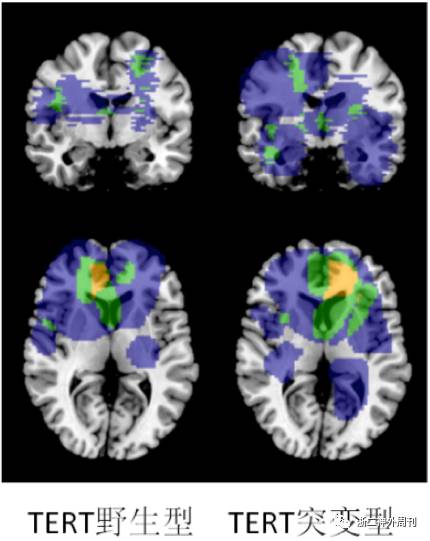

进一步我们分析肿瘤分子特征同肿瘤的位置关系。图4显示IDH基因突变同肿瘤位置的关系。图5显示TERT基因启动子突变同肿瘤位置的关系。图6显示染色体1p19q共缺失状态同肿瘤位置的关系。

图5. 不同TERT基因启动子突变状态的胶质瘤的位置分布特征。